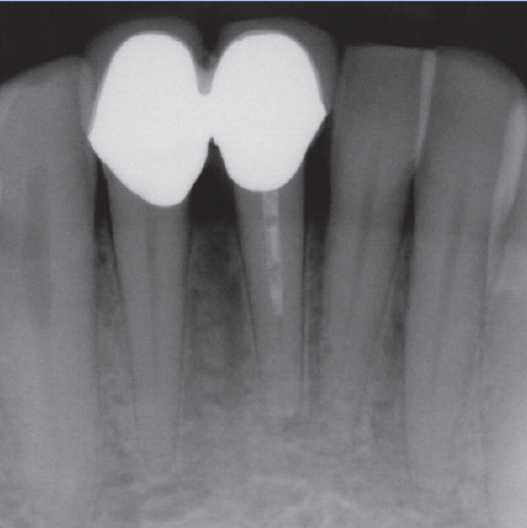

Before

Before Root Canal treatment